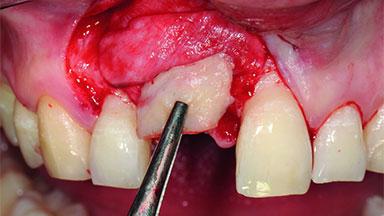

A 36-year-old male patient with a compromised maxillary central incisor was referred by his general dentist for consultation. The patient’s chief complaints were the gradual debonding of a temporary crown on the right central incisor and unsatisfactory esthetics due to an increasing diastema between the right central and lateral incisors. The patient reported a traumatic event some years previously, when a crown had been placed after root-canal treatment. The referring dentist wanted to provide a new crown restoration, but was concerned about the condition of the residual root. Anamnesis was negative for any other dental or periodontal pathology in the remaining dentition. The patient reported taking no medications: He was a smoker (10 to 15 cigs/day) and had realistic esthetic expectations.

Bone Augmentation Horizontal|Simultaneous|Staged

Augmentation Materials Xenogenous|Membrane

Bone Volume Deficient horizontally, requiring prior grafting